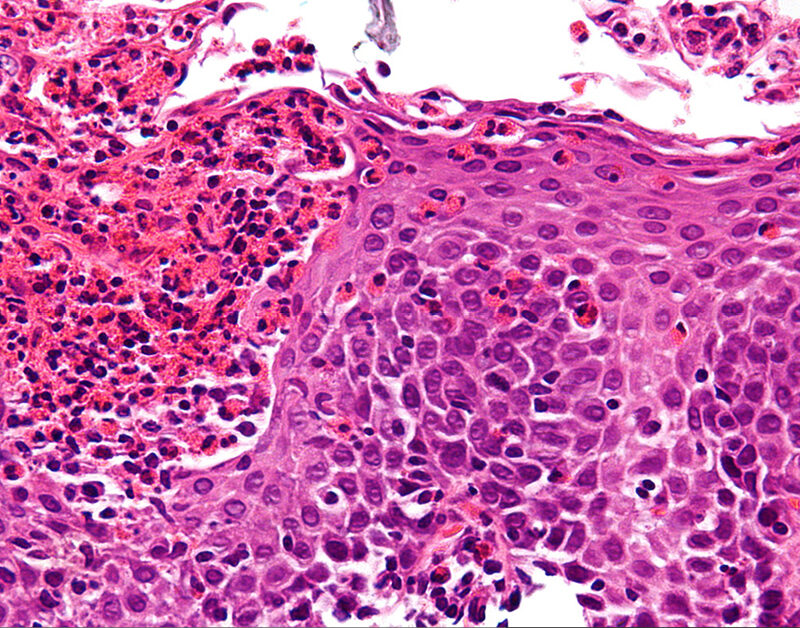

Eosinophilic Esophagitis image from Wikipedia